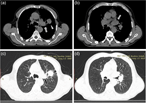

A rare case of giant cell lung carcinoma with intracardiac extension via the pulmonary vein and thrombus formation

Vasileios Leivaditis and others

Journal of Surgical Case Reports, Volume 2018, Issue 6, June 2018, rjy144, https://doi.org/10.1093/jscr/rjy144